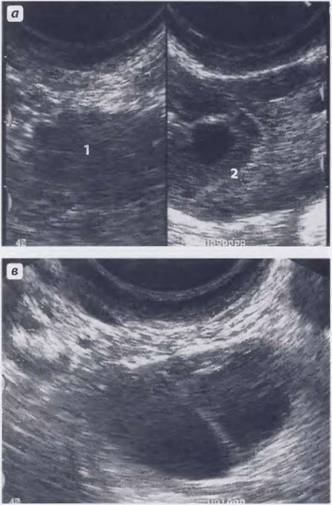

Такие образования хорошо видны при ультразвуковом исследовании, МРТ. Но во время УЗИ не видны ткани, из которых состоит образование, поэтому о наличии кальцината можно только предположить. Такая ситуация требует дополнительного обследования женщины, чтобы исключить заболевания гораздо серьезнее, чем наличие отложений солей кальция.

- Исследование органов, расположенных в малом тазу, при помощи ультразвука. Кальцинаты матки на УЗИ будут заметны.

- Ультразвуковое исследование органов малого таза и в первую очередь самой матки. Требуется во всех случаях.

Ультразвуковое обследование позволяет случайно выявить образования и предположить наличие кальцинатов. Дифференциальную диагностику проводят с полипами матки.